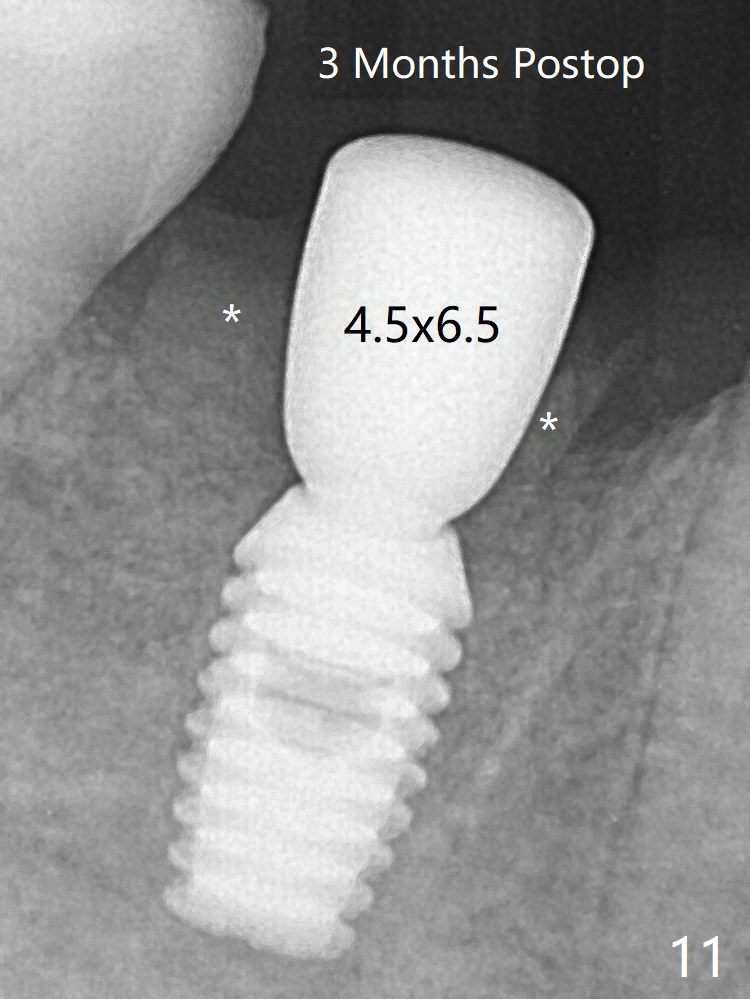

Following 4.5x11.5 mm drill, a 4.5x8 mm Bicon implant is pressed fit; its stability is lightly enhanced with placement of sticky bone in the remaining sockets (Fig.4 *) and around the black plug (Fig.5 P). The implant appears to remain covered by the bone 3 months postop (Fig.11 (* socket shield)). Cortical bone starts to form crestal 7 months postop (Fig.12 arrowheads, coronavirus).